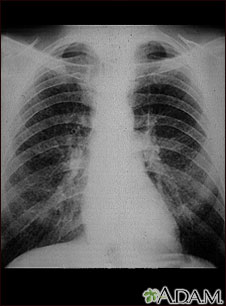

A chest x-ray is an x-ray of the chest, lungs, heart, large arteries, ribs, and diaphragm.

Images